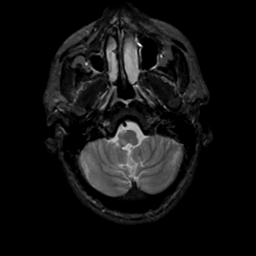

MR Study #8, March 31, 1991 -- Slice #7

[Home][Help][Clinical][Tour 1][Tour 2] Slice 7